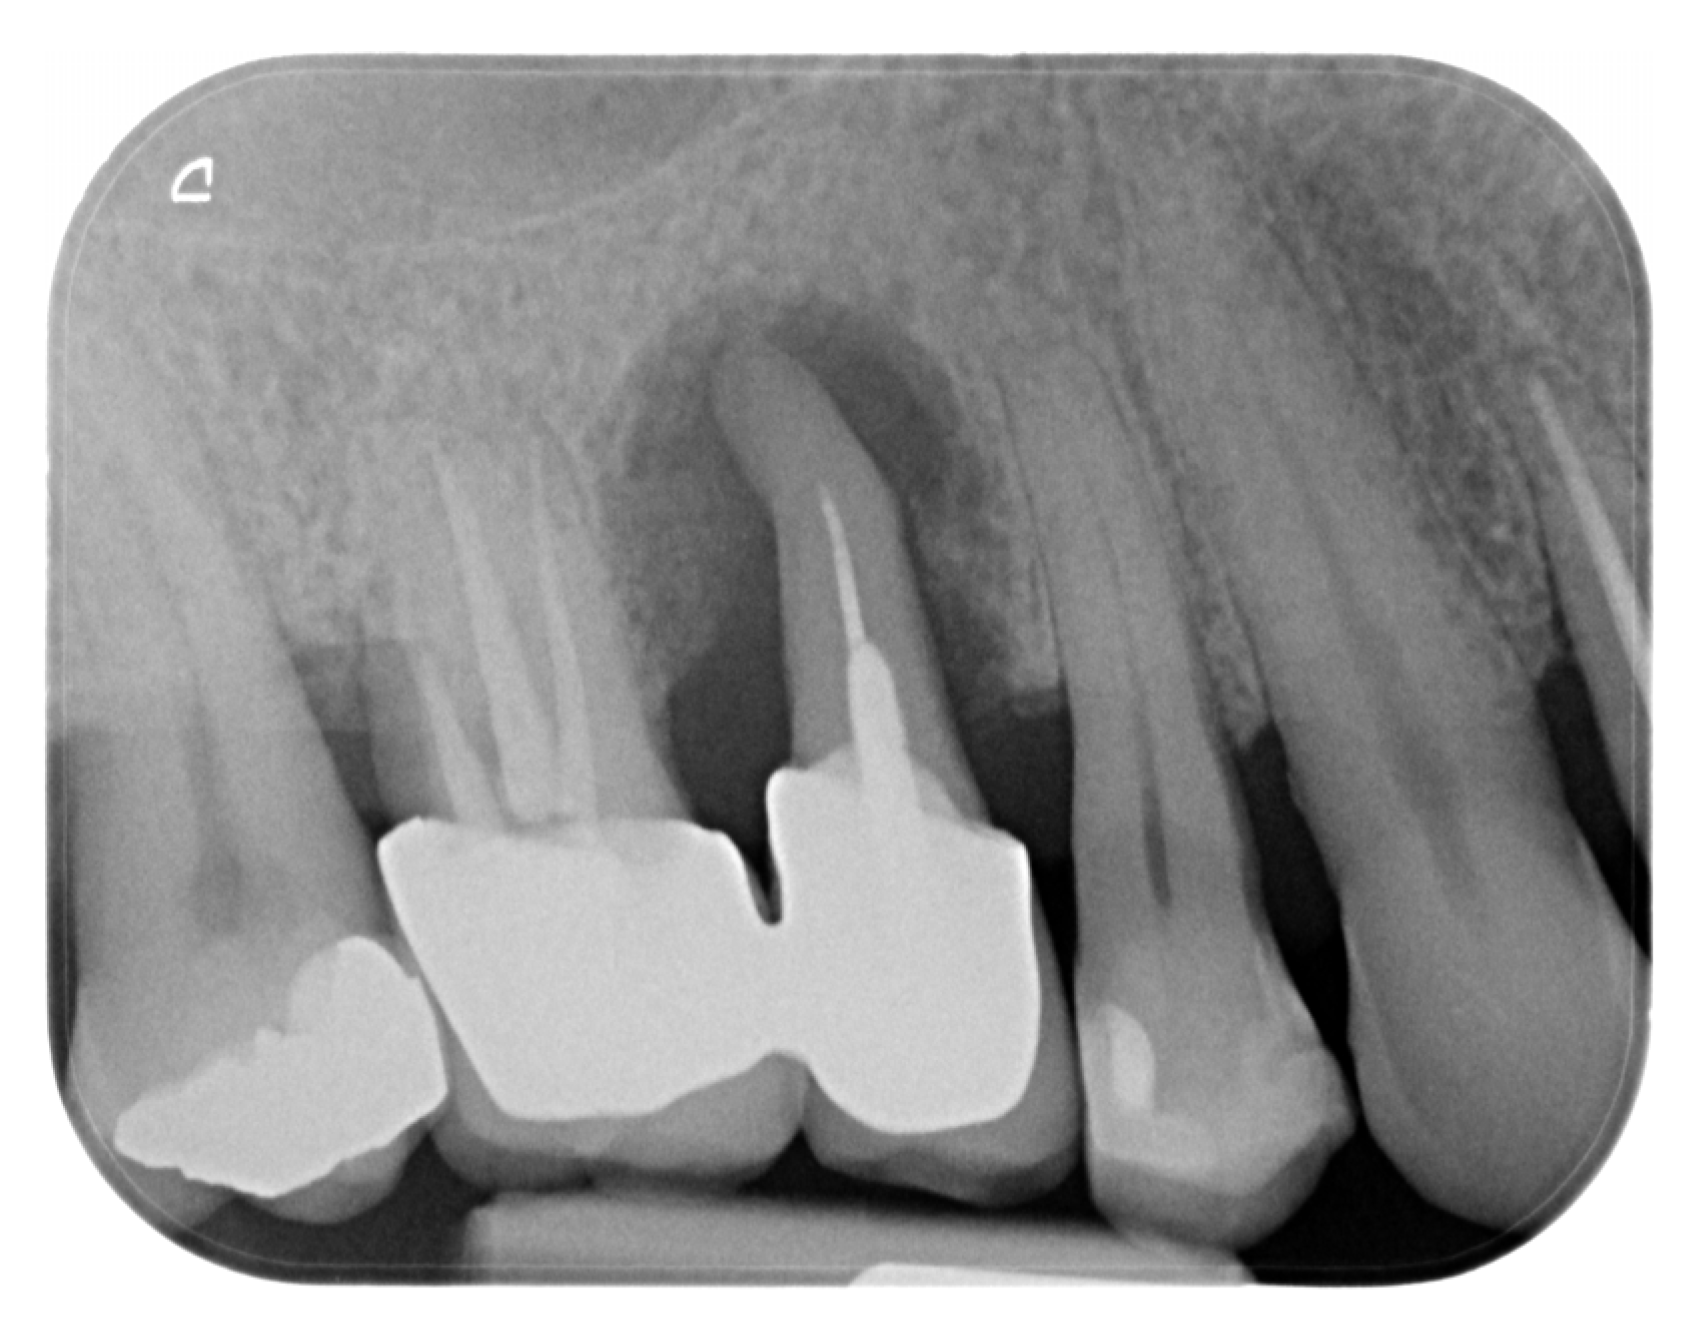

2. Materials and Methods—Clinical Case